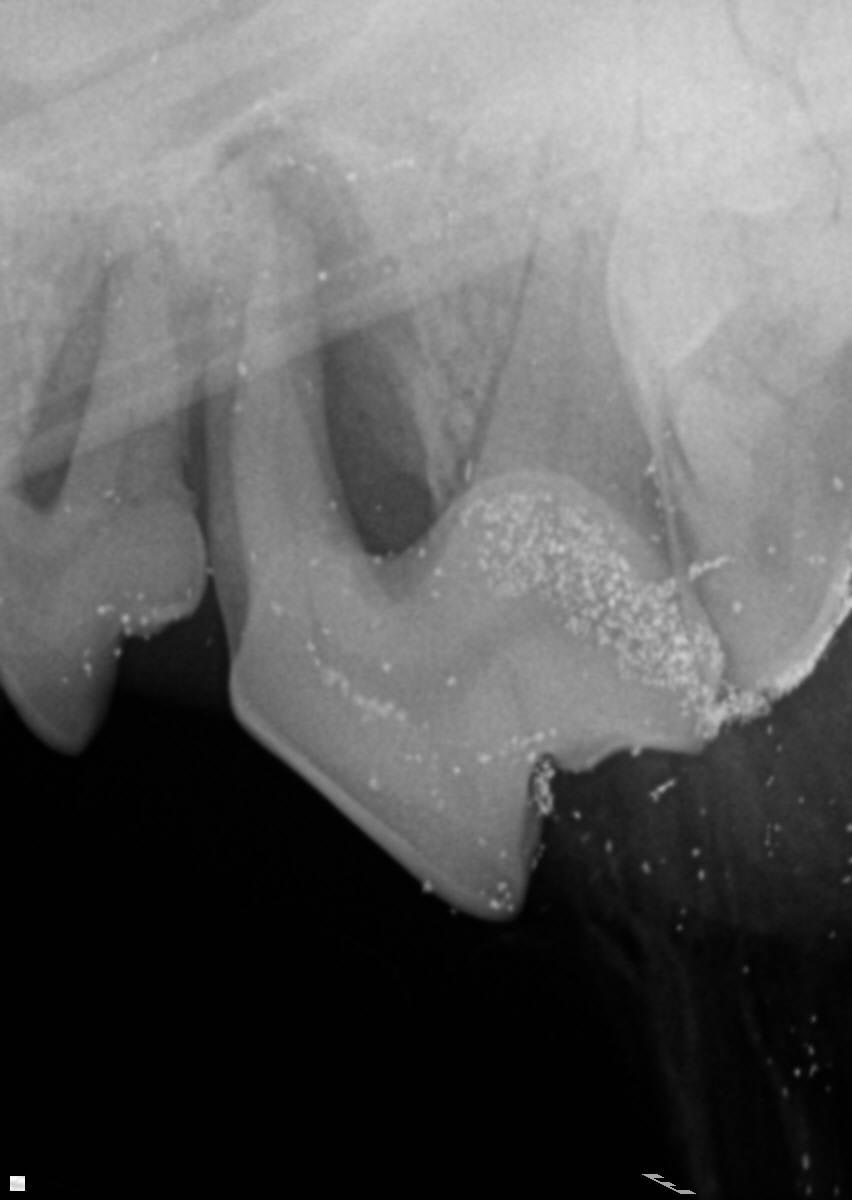

Our dog had his teeth cleaned a few months ago. During the cleaning the vet had concerns about his carnassial teeth. He said 1 root was exposed, 1 root was good, and 1 root was so-so. He said it was somewhat rare and initially said we could "wait and see" or go to an expert. However, he later changed his mind and said they should be removed. I wondering if they really need to come out. My dog does not appear to be in any pain.

Based on the attached pictures, I would recommend removal of the carnassial tooth as well as the too the next to it. There is significant loss of bone around the roots and should really come out now. The vet may have recommended referral to a vet with more experience as these teeth can be challenging to remove due to their size, location, and number of roots.